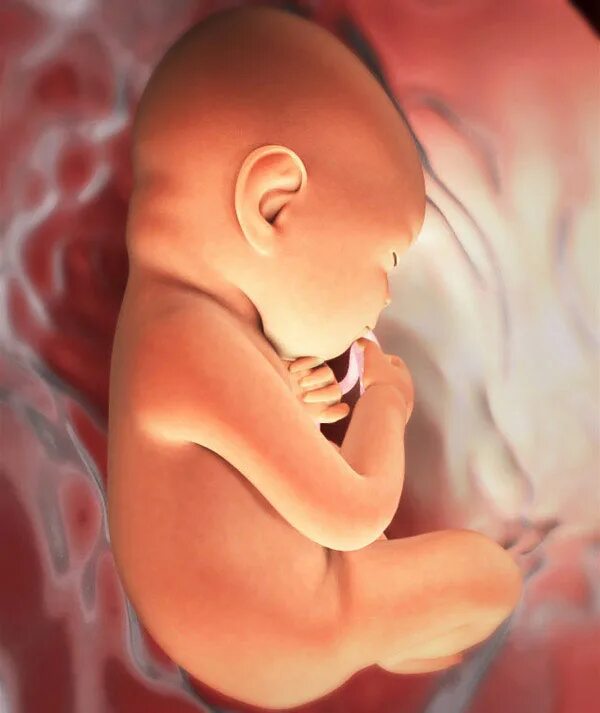

Как выглядит ребенок в 34 недели